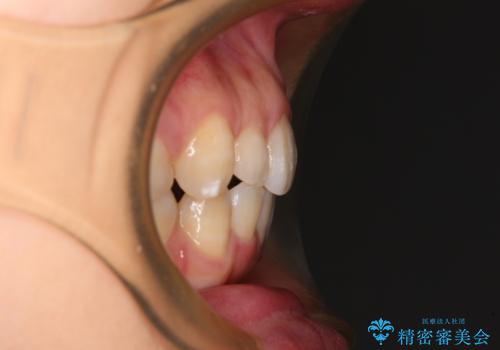

- 下顎前歯を中心に、以前行った矯正治療の後戻りが気になるとのことで来院された患者様です。

後戻りは軽度であったため、インビザライン・ライトにて治療を行うこととしました。